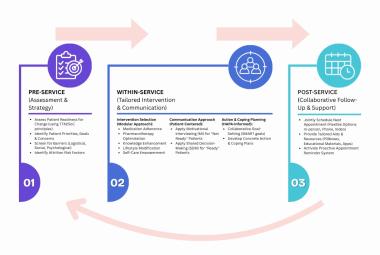

One of the notable complications of impacted mandibular third molar (MTM) is distal caries of the mandibular second molar (MSM) which can eventually lead to its early loss. The present study aimed to investigate the incidence of dental caries in MSM associated with impacted MTM and to propose an assessment protocol for MTM management. Patients’ dental records with dental panoramic tomography (DPT) imaging were studied retrospectively, in total 583 MTM images were evaluated. The presence of MSM distal caries, patient’s details, impaction depth, pattern and angulation of MTM and the distances between distal MSM and mesial MTM were assessed. Logistic regression analysis was performed on the data set. The highest caries incidence was observed in mesioangular impacted MTM (34.1%). Majority of the caries found were Level A (27.9%) and Class II (27.0%). The highest distance between distal MSM and MTM contributing to caries was 0.70-0.99 cm (31.9%). Patients’ age, angulation, pattern and depth of impacted MTM are the predictors which significantly increase the caries incidence in MSM (p<0.05). Prophylactic removal of MTM should be proposed when the distance of mesial impacted MTM and distal MSM is around 0.70-0.99 cm, and is mesially angulated with IIA classification.

Salah satu komplikasi ketara gigi geraham bongsu rahang bawah (MTM) yang tidak tumbuh sepenuhnya (terimpak) ialah karies distal pada geraham kedua rahang bawah (MSM) yang akhirnya boleh menyebabkan kehilangan awal gigi tersebut. Kajian ini bertujuan untuk menyiasat kejadian karies gigi pada MSM yang mempunyai kaitan dengan MTM terimpak serta cadangan penilaian langkah pengurusan berkaitan dengan MTM. Rekod pergigian pesakit bersama gambar panoramik pergigian telah dikaji secara retrospektif, dengan sejumlah 583 imej MTM telah dinilai. Kewujudan karies distal MSM, butiran pesakit, kedalaman impaksi, corak dan sudut MTM serta jarak antara MSM distal dan MTM mesial telah dinilai. Analisis regresi logistik dijalankan ke atas set data. Insiden karies tertinggi diperhatikan pada MTM terimpak mesioangular (34.1%). Kebanyakan karies yang ditemui ialah Tahap A (27.9%) dan Kelas II (27.0%). Jarak tertinggi antara MSM distal dan MTM yang menyumbang kepada karies ialah 0.70-0.99 cm (31.9%). Umur pesakit, sudut, corak dan kedalaman MTM terimpak ialah pembolehubah yang meningkatkan insiden karies pada MSM secara signifikan (p<0.05). Cabutan pencegahan gigi MTM sepatutnya dicadangkan apabila jarak antara MTM terimpak mesial dan MSM distal adalah sekitar 0.70-0.99 cm, dan MTM bersudut mesial dengan klasifikasi IIA.